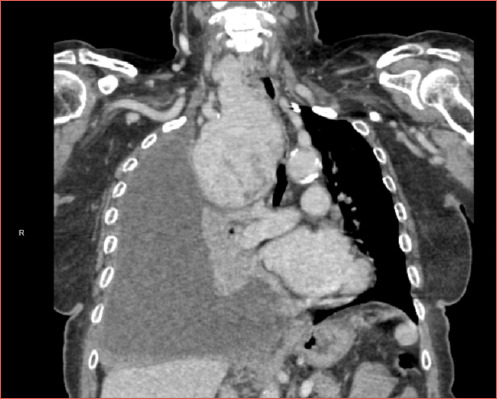

Objective: Intrathoracic goiters (ITGs) pose numerous challenges to head and neck surgeons due to the intricate relationships with major vessels and other mediastinal structures. Surgical excision remains the mainstay of treatment and we herein present an update on this topic.

Results: Transcervical excision is the commonest approach for treating ITGs, yet the potential need for a transthoracic approach must be always kept in mind. An acceptable rate of postoperative complications is expected if surgeries are carried out by experienced and dedicated surgical teams.